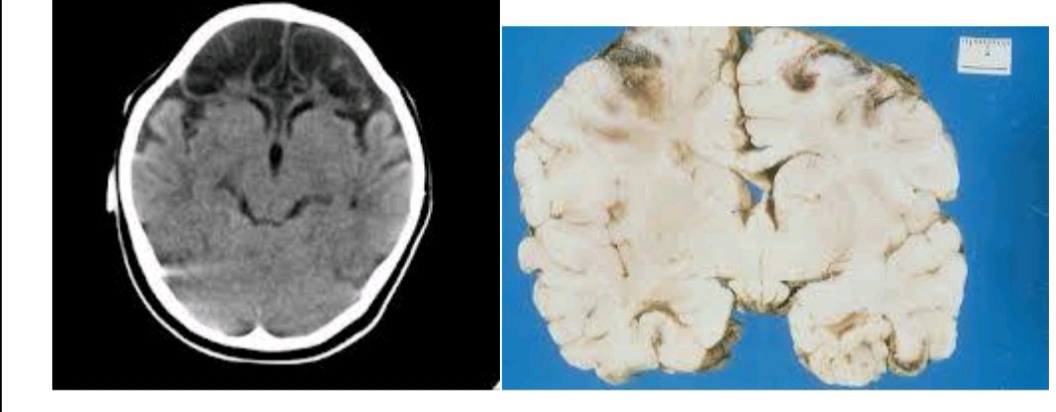

颈内动脉闭塞并发脑梗塞图片

图片尺寸640x515